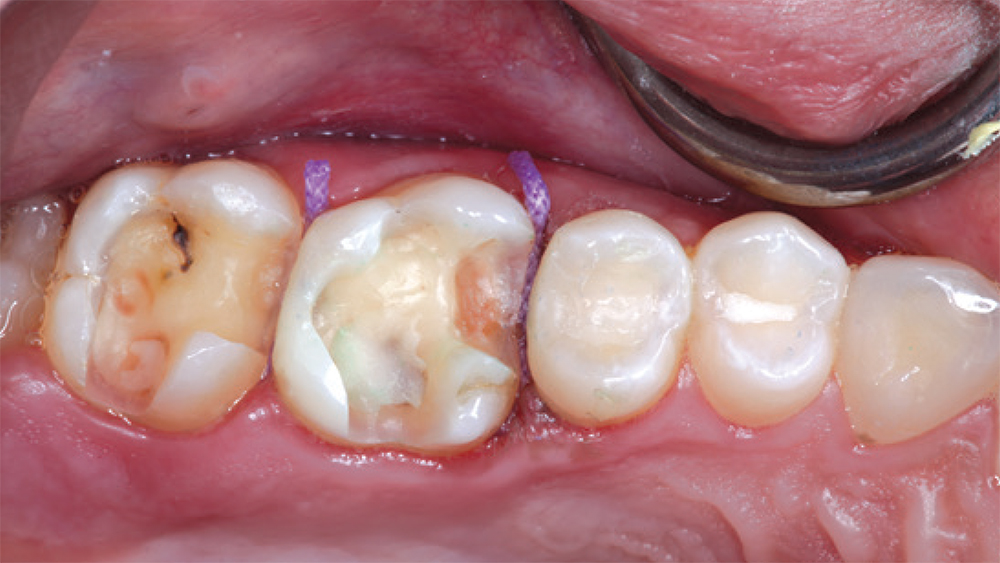

teeth #2

teeth #3

patient's fillings on teeth #2 and #3

In this case, the patient’s fillings on teeth #2 and #3 were removed and the teeth were prepared. During the same appointment, the doctor scanned the patient’s teeth and fabricated onlays from CAMouflage NOW milling blocks using the glidewell.io In-Office Solution. The onlays were delivered following a scientifically validated bonding protocol, maximizing the longevity of the nanohybrid composite restorations.